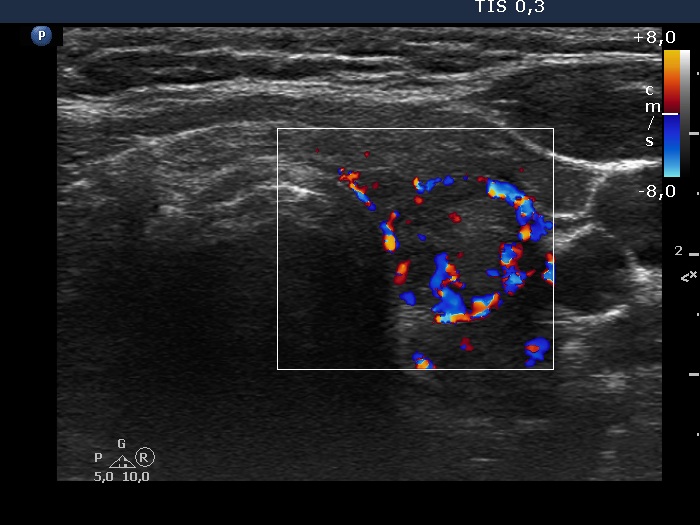

Patient referred for evaluation of thyroid nodule - final diagnosis Hashimoto's thyroiditis - Case 29. (ultrasonographic picture 7)

Left lobe, longitudinal scan, color Doppler mode. The echonormal area presents perinodular and intralesional blood flow.